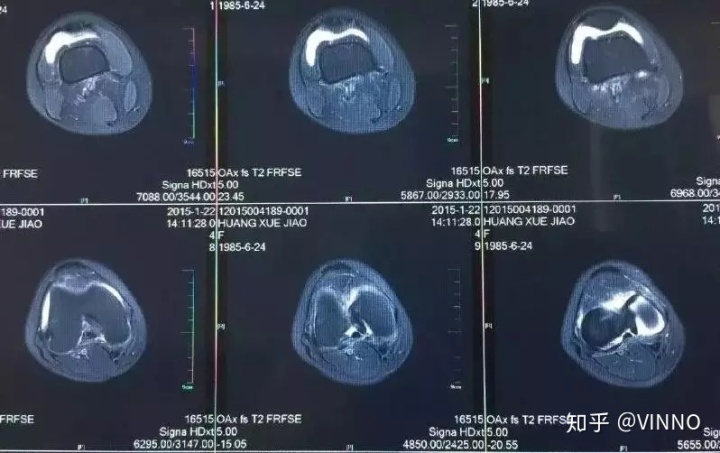

▲ 这是CT断层扫描影像

成像原理:记录分层穿过人体的X光,通过电脑计算后二次成像,优点是可以分层看,显示出更多的组织信息,但也有一定的局限性。